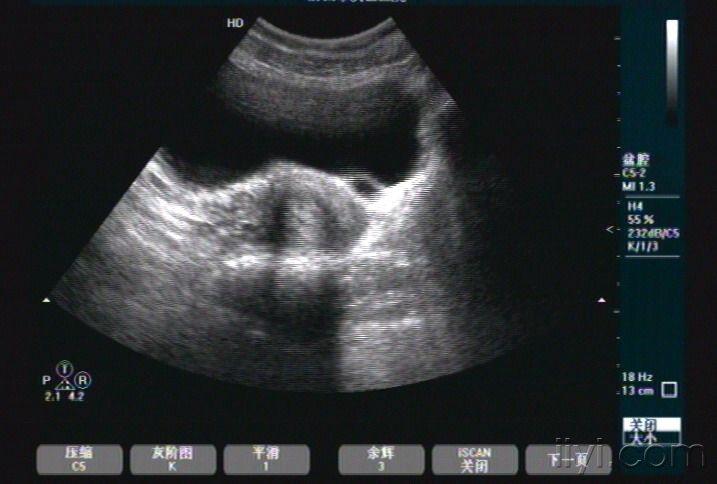

腹部超声:膀胱输尿管反流_扩张

输尿管囊肿 - 超声医学讨论版 - 爱爱医医学论坛

超声故事:儿童输尿管囊肿_扩张